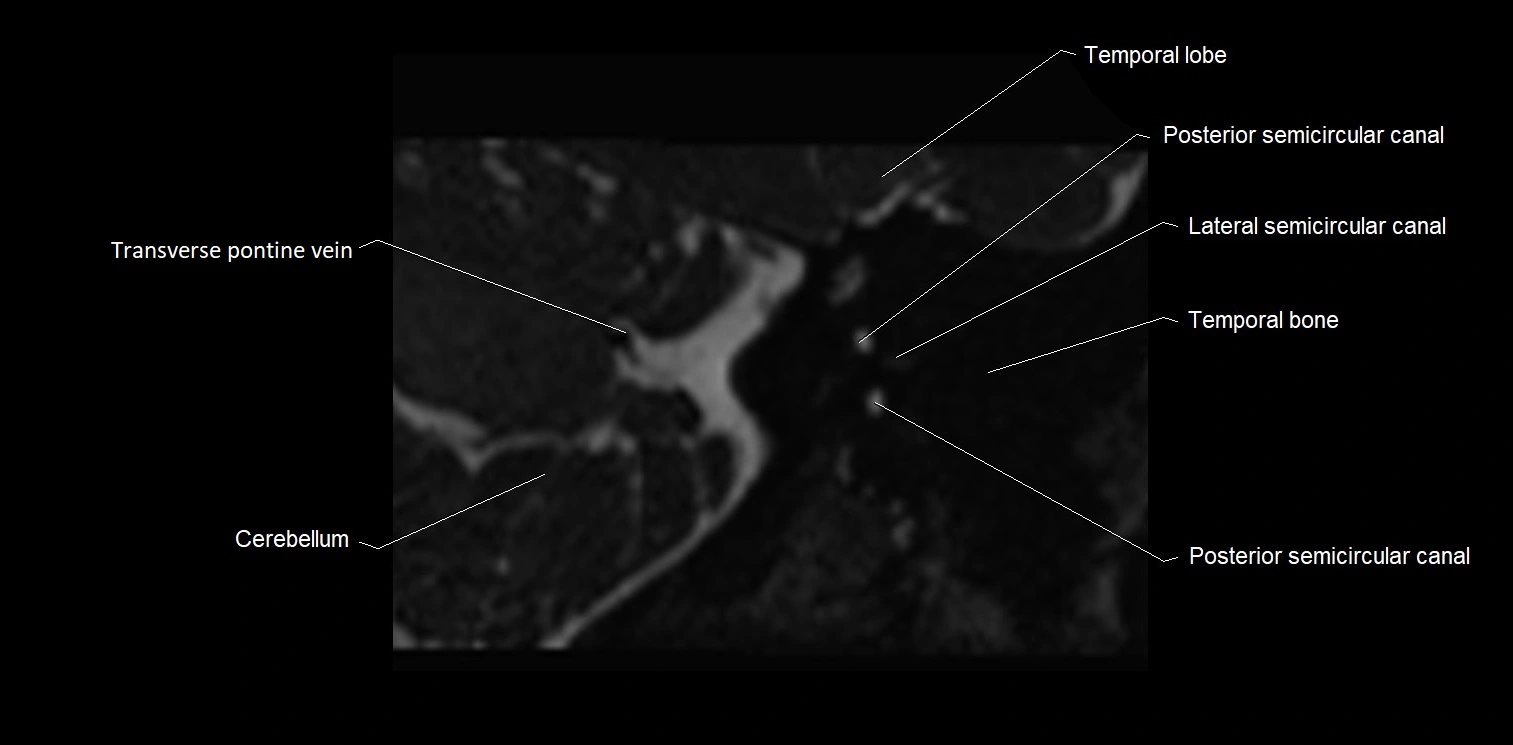

MRI images

image